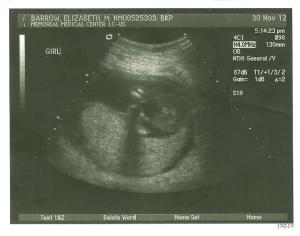

Mike and I love this picture because you can make out her cute lips and nose. Hence the nickname, Lil’ Peck.

The tech put this picture in an envelope and kept telling me she wasn’t completely sure, but this was her suspicion as to what she thought the gender was. Mike and I walked out to the car and opened the envelope together. It’s a GIRL!